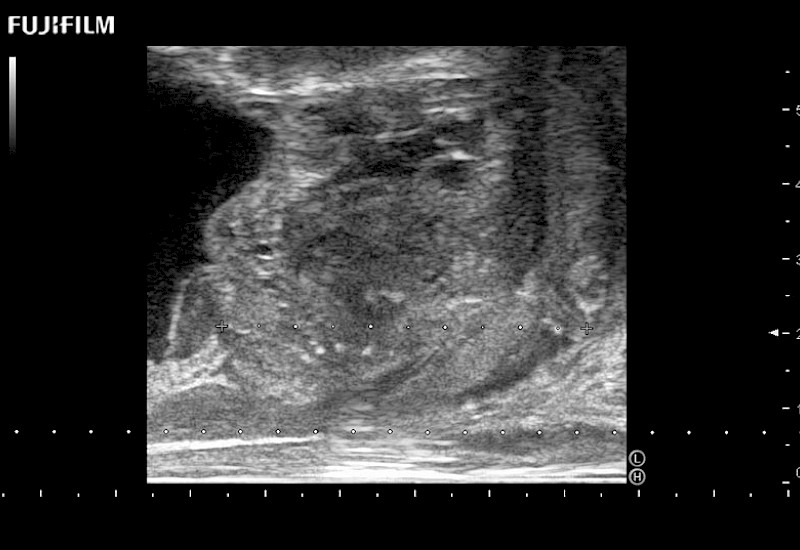

38mm footprint is ideal for scrotal and penile doppler imaging

Designed for high-resolution imaging of the scrotal and penile regions. This advanced transducer offers exceptional image quality, user-friendly features, and specialized functionalities to support accurate urological diagnostics and enhance patient care.